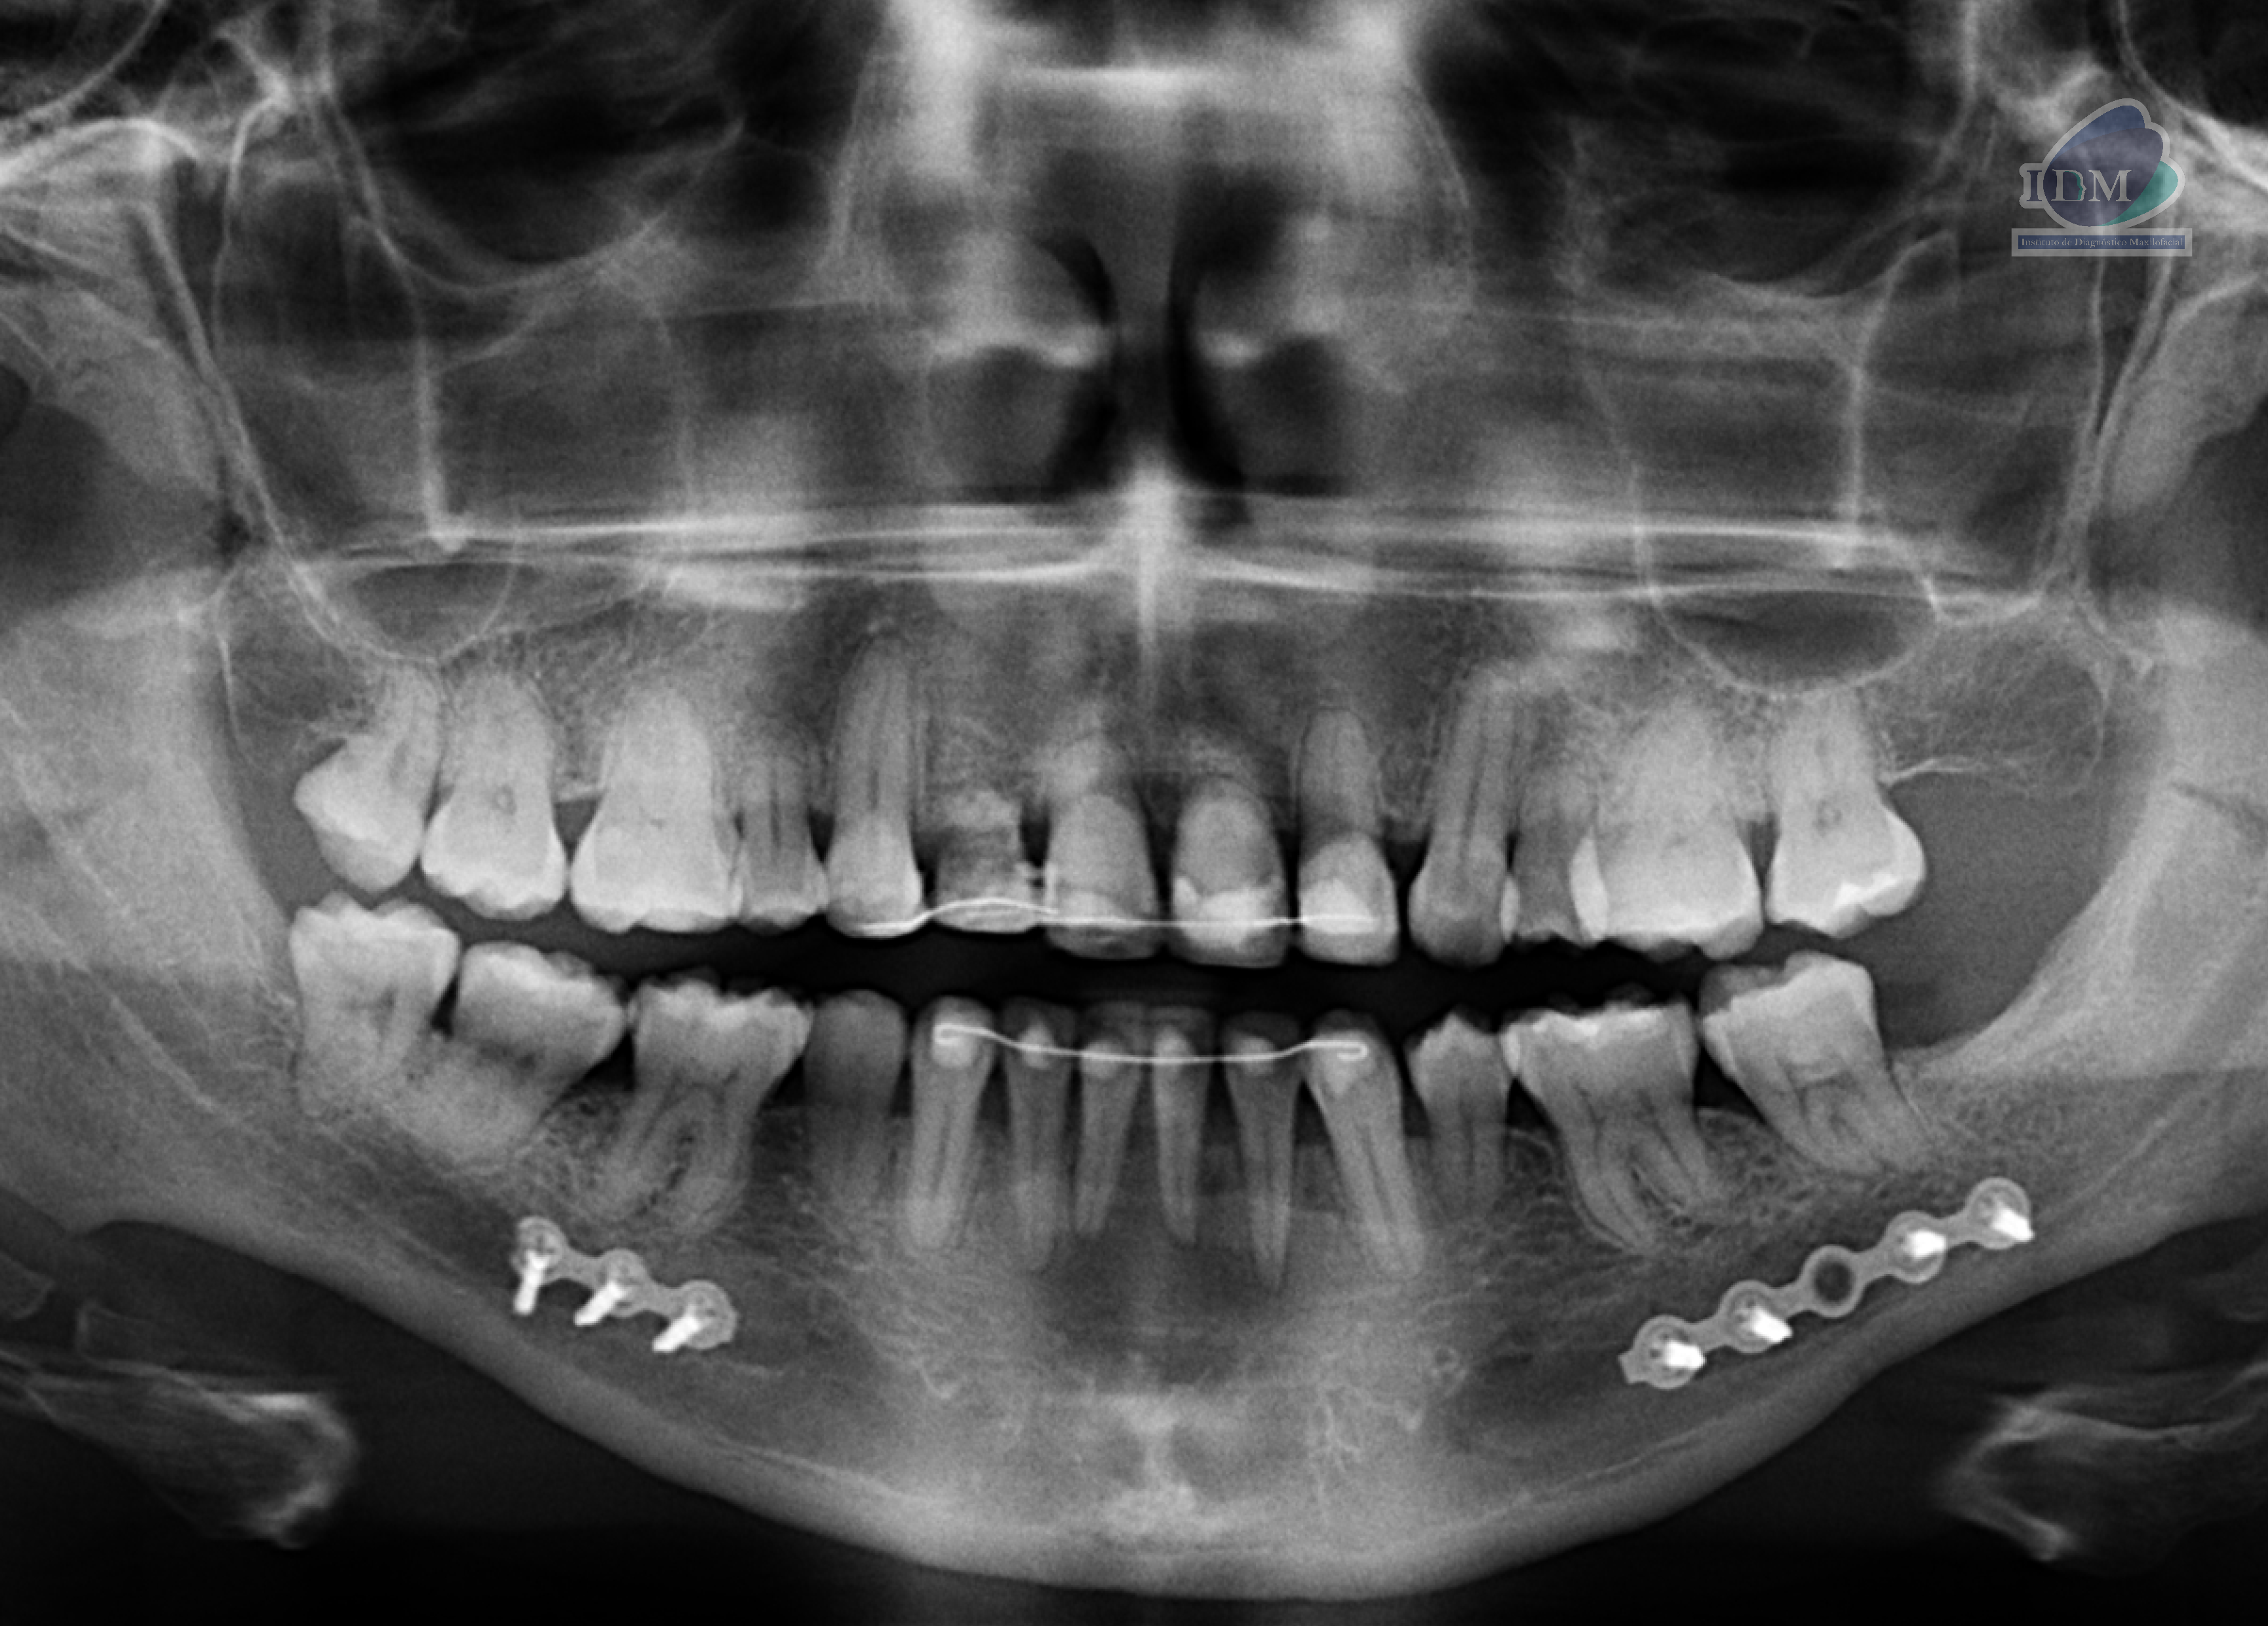

Radiografia Panorámica

A la evaluación de la radiografía panorámica se evidencia una disminución generalizada de la longitud radicular así como la presencia de alambre de fijación en sector dentario anterior y ausencia de algunas piezas dentarias. Siendo lo más resaltante la presencia de un tejido mineralizado en zona cervical de ambos lados, presentando con un patrón lineal pseudoarticulado.

- Mineralización bilateral de la cadena estilohioidea del tipo pseudoarticulada.

Tipo II o pseudoarticulado; en la que la apófisis estiloides está unida al ligamento estilomandibular o al ligamento estilohioideo por una sola pseudoarticulación, la cual se encuentra localizada al borde inferior de la mandíbula (de manera tangencial).